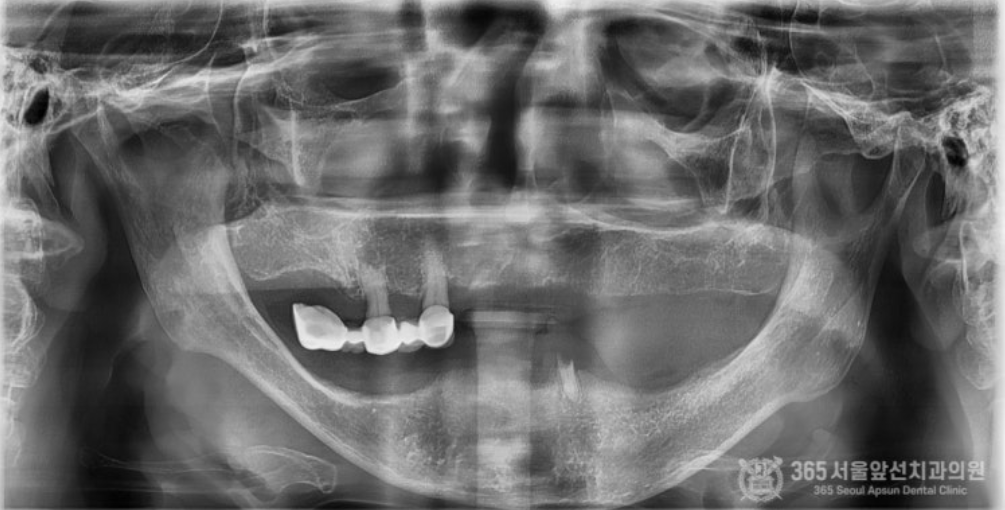

골다공증이 심해서 임플란트가 불가능하다는 이야기를 들었어요. 임플란트가 가능할까요? 상기 환자분은 골다공증으로 치료를 받고 계신 환자분이십니다. 골다공증제를 복용하고 계시거나, 골다공증 치료제 주사를 맞고 계실 경우 임플란트 치료시 고려되어야 하는 것은 널리 알려진 사실입니다. 결론부터 말씀드리자면 골다공증 치료를 받고 계시더라도 주치의와 상의해서 스케줄을 조율한다면 대부분 큰 무리 없이 임플란트 치료를 받으실 수 있습니다. 촬영일시 : 2024.07.05. 처음 내원 당시 엑스레이 사진입니다. 한눈에 보기에도 뼈가 거의 없어서 임플란트 치료가 쉽지 않으신 환자분입니다. 또한 엑스레이에서 보다시피 뼈의 밀도가 낮아서 뼈가 어둡게 보입니다. 골다공증 병력을 가진 환자분들에서 종종 나타나는 국소골다공성골수결손(Focal osteoporotic bone marrow defect) 양상을 보이셨던 환자분입니다. 촬영일시 : 2024.07.05. 임플란트 식립시 뼈의 모습입니다. 텅 빈 공간에 임플란트가 덩그러니 있는 듯한 모습이지만, 해당 공간은 임플란트를 식립하기 위해 뼈에 구멍을 낸것이 아니라 골수 결손으로 인해 원래부터 빈 공간이었던 부분입니다. 그 만큼 뼈의 상태가 매우 좋지 않았다는 것을 알 수 있습니다. 촬영일시 : 2024.07.05. 아래 앞니 부위도 뼈가 매우 얇아서 임플란트 식립시 뼈를 쪼개서 식립(ridge splitting)해야 할 정도로 매우 상태가 좋지 않았습니다. 촬영일시 : 2024.07.11. 수술이 잘 마무리된 후 엑스레이 사진 및 구강 내 사진입니다. 촬영일시 : 2024.11.11. 4개월 후 최종 보철물을 제작했습니다. 위턱은 전체임플란트로 치료를 마무리 지었고, 아래턱은 임플란트 브릿지와 틀니를 조합하여 잘 마무리해 드렸습니다~ ^^ 촬영일시 : 2024.07.05. / 2024.11.11. 구강 내 전후 비교사진입니다. 완전히 달라진 전후 모습을 비교할 수 있겠습니다. 오늘은 골다공증으로 인해 국소 골다공성 골수결손(focal osteoporotic bone marrow defect)이 발생된 환자분의 전체 임플란트 치료 증례를 소개해드렸습니다. 수 없이 많은 전체 임플란트 환자분들을 치료 하다보면 전신질환으로 인해 치료가 쉽지 않은 경우가 종종 있습니다. 하지만 질환을 잘 이해하고 있는 치과의사와 함께 한다면 치료를 잘 마무리 하실 수 있으니 걱정안하셔도 되겠습니다. 365서울앞선치과 대표원장 강동우였습니다. 감사합니다 ! [ 치료기간: 2024년 7월5일 ~2024년 11월 11일 ] ※ 365서울앞선치과의원의 모든 컬럼은 각 진료과 의료진이 직접 작성합니다. 365서울앞선치과의원 임상 케이스 게시물은 환자분께 의학적으로 정확하고 상세한 정보를 드리기 위해 각 진료과 의료진이 직접 작성하며, 모든 증례 사진은 본원 의료진이 직접 시술한 증례를 촬영한 것으로, 의료법 제23조, 제56조에 의거하며 환자분의 동의를 얻어 포스팅에 사용하였습니다. 또한 해당 케이스는 본 환자분의 치료 결과이며, 환자 상태에 따라 치료의 결과는 달라질 수 있습니다. |